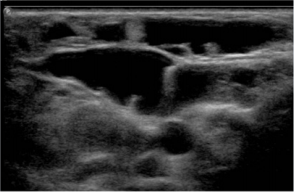

A six-year-old female patient presented with a large congenital right hemifacial tumor, with slow progressive growth (Figure 1). The sequential imaging control with US and MRI exhibited a LM with macrocystic and microcystic components in the right hemiface (Figures 2 & 3). The patient displayed an inadequate response to treatment with Sildenafil. Also, multiple sclerotherapy sessions were performed with suboptimal tumor control. At the four years of age, she showed a persistent volume increase of the LM in the right maxillary and temporal area, compromising vision. Emphasis on the importance of an effective treatment was made due to the risk of amblyopia. As new imaging tests showed a progressive growth of the lesion. Supplementary sclerotherapy sessions were made with partial response. Because of the ophthalmic urgency and the poor response after several treatments, a Rapamycin based therapy was proposed to the family, offering to install a local device which was safely used previously in cardiac procedures. They signed the informed consent approved by the ethics committee. The interventional radiologist installed an intralesional Rapamycin stent (Ultimaster 2.5 mm diameter min. guiding catheter 1.42 mm Lot 170726) (Figure 4). The percutaneous guide was used through the lymphatic cyst. The procedure was well tolerated, without side effects. Clinical improvement was immediately evident, with substantial pain relief, along with a significant decrease in the tumor size and restored orbital aperture (Figure 5). Two US follow ups after the procedure, showed small cysts and decreases in the volume of the macrocysts. Some inflammatory change in the periorbital and cheek subcutaneous tissue and no abnormal vessels are depicted in Doppler color US (Figures 6 & 7).

Figure 2: US shows multiple confluent thin wall cysts in the right hemiface concordant with macro and microcystic LM.

Figure 3: US shows multiple confluent thin wall cysts in the right hemiface concordant with macro and microcystic LM.

In the imaging diagnosis of vascular malformations ultrasound represents a fundamental pillar, based in the gray scale imaging and Doppler color. Also, the MR is very important specially in extense, severe or vital structures compromise [2]. US allows evaluating the presence of cysts, the different layers compromised, presence of solid tumors or calcification, small part hypertrophy and vascular pattern of the lesion. When a vascular malformation is suspected the existence of anomalous arterial or venous vessels can oriented to a high or low flow malformation. In LM the presence of cysts is the key point. US can differentiate in microcystic (cyst less than 1 cm), macrocystic (cysts bigger than 1 cm) o mixed LM, [1] and can suggest the presence of LM complications. In US we can observe micro or macrocysts distributed in a focal area or more spread areas. The cysts are anechogenic with thin walls. Sometimes some echoes or level inside the cyst can be observed. These are more frequent in the presence of complications. The cyst can be located in the superficial layers or depth in the body. The subcutaneous location can be associated to adipose tissue hypertrophy. In Doppler color small thin venous vessels can be observed in the septa between the cyst. When the vascular malformation is a combined malformation abnormal venous or arteries can be present.